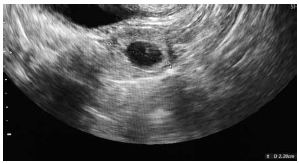

C.V.R.S., 36 anos, G VII P VI (6N) A0, IG cr: 6 semanas,deu entrada no PSGO com sangramento vaginal há cerca de 1 semana. Sem ultrassom prévio. Ao exame físico: especular: colo uterino sem lesões, mínima quantidade de sangue vermelho escuro em fórnice posterior. TV (toque vaginal) bimanual: colo impérvio, grosso, posterior. Ausência de dor à mobilização do colo uterino. Abdome: DB negativo, dor leve à palpação profunda de hipogástrio. Submetida à ultrassonografia transvaginal (imagens a seguir: figuras 1, 2, 3, 4) e beta HCG quantitativo: 9 000 UI/mL. Resultado de beta HCG 24h antes: 7 000 UI/mL.

Figura 3 (zoom de região anexial E; sem visualização de embrião)